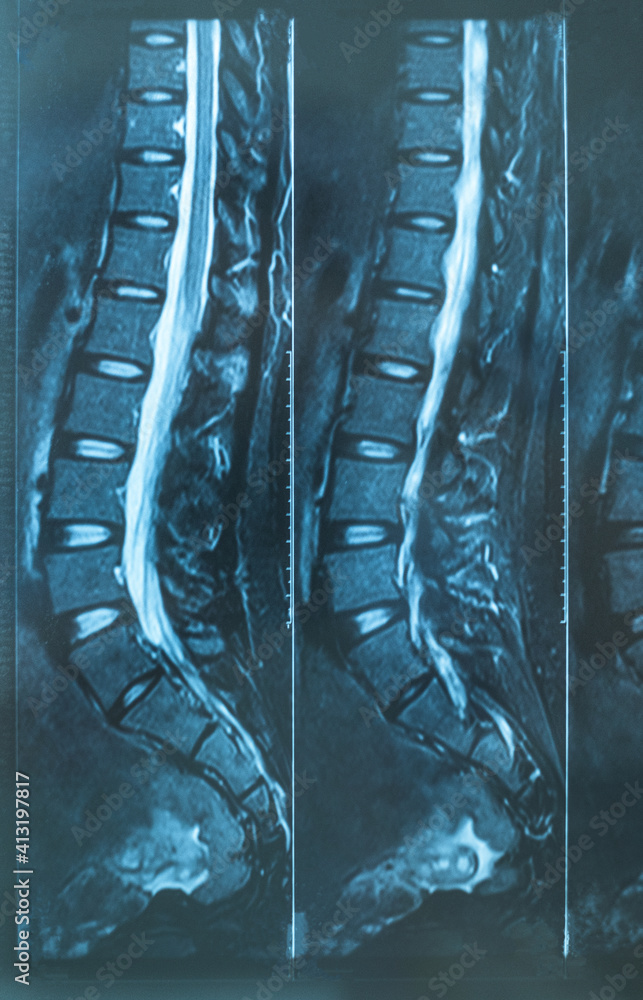

From stock.adobe.com

X ray MRI of lumbosacral spine (LS spine) case of low back pain Chronic Back Pain Normal X Ray the initial evaluation, including a history and physical examination, of patients with chronic low back pain should attempt to place patients into one of the following. low back pain is the second most common complaint in the united states, with a lifetime incidence of 80% to 85%. Information about spinal alignment can be obtained under static and. Patients. Chronic Back Pain Normal X Ray.